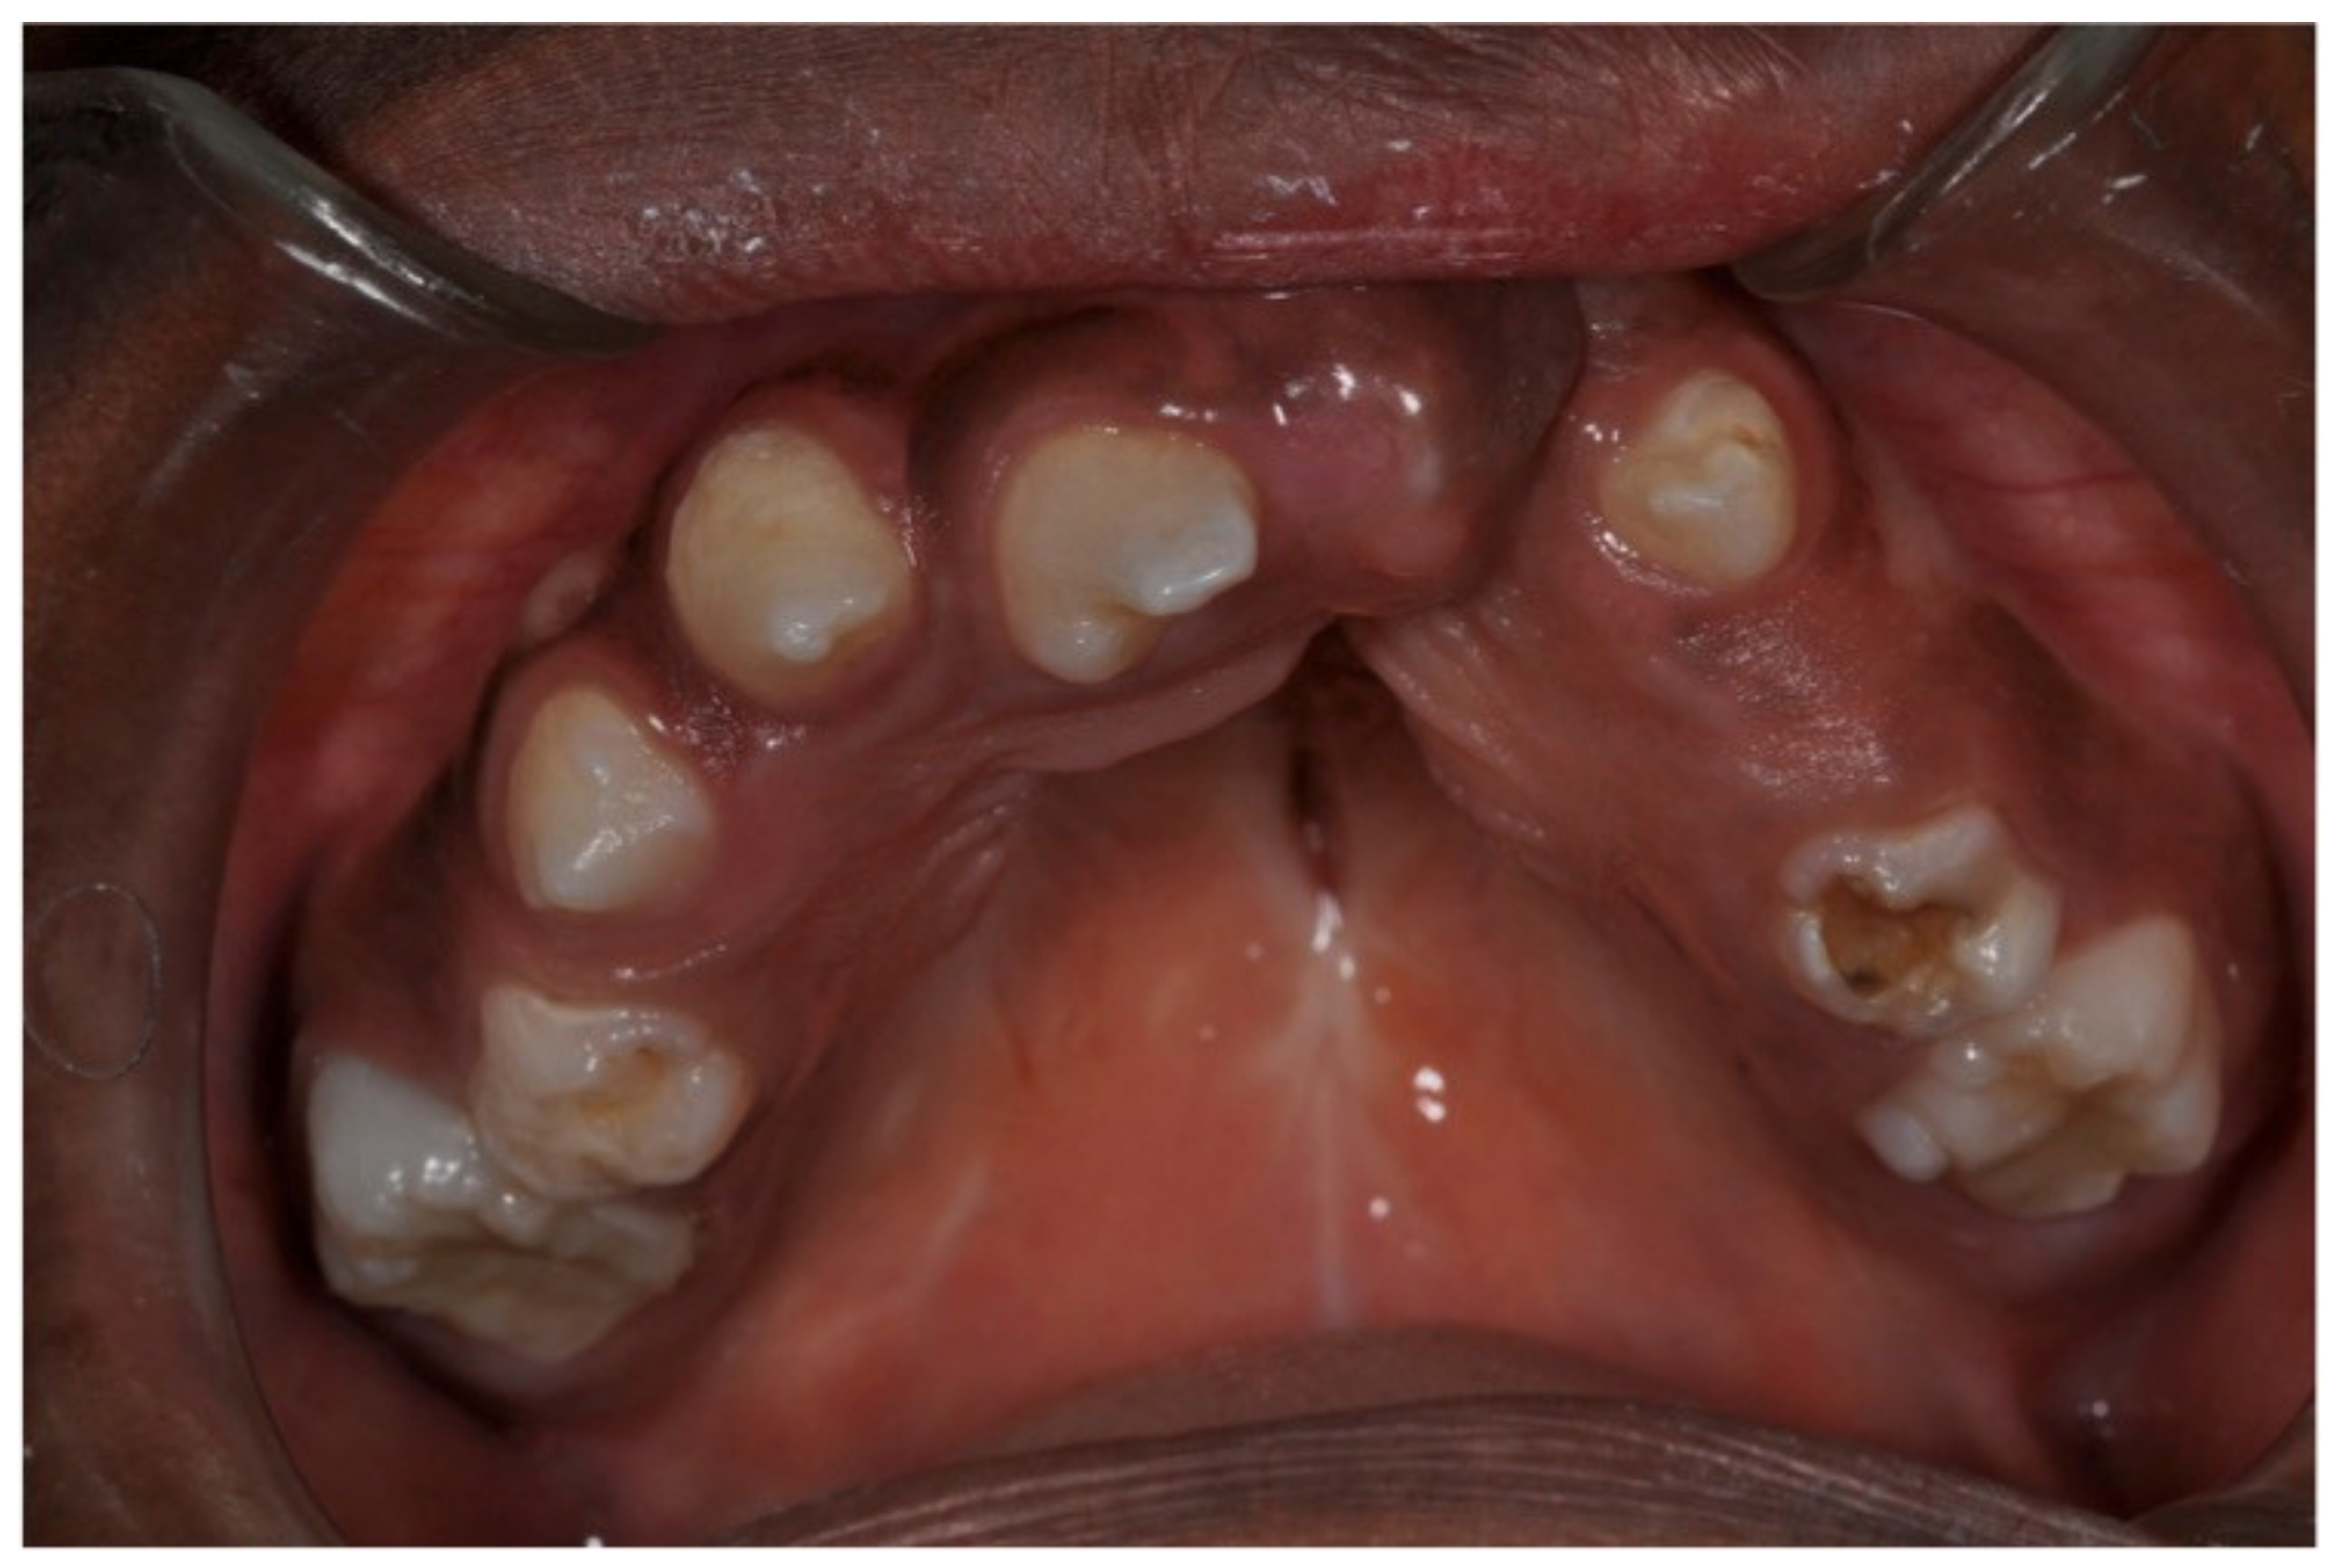

Other associated anomalies may include the delayed exfoliation of the deciduous elements (Figure 4) and eruption delays.

Figure 4. Delayed exfoliation of the deciduous elements and eruption delays.